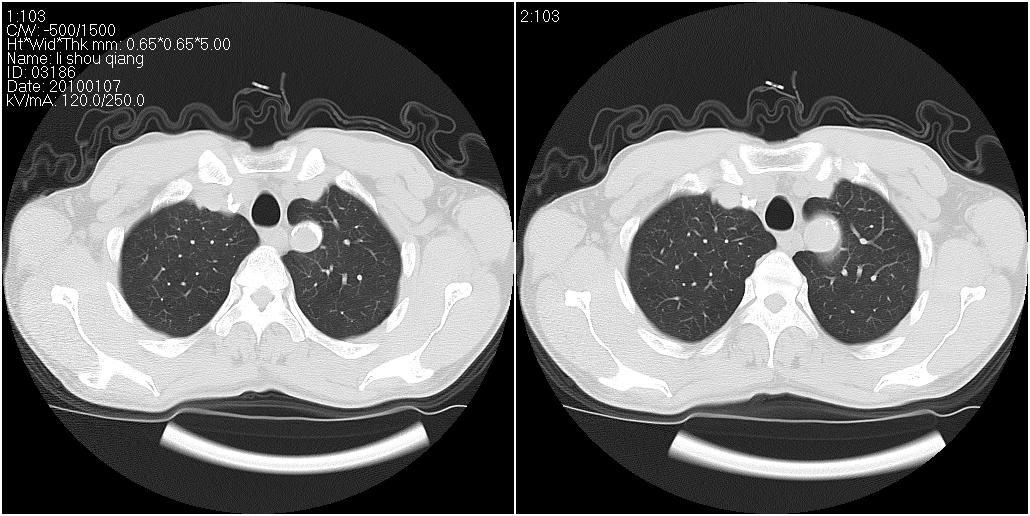

右肺中叶外侧段见一不规则的软组织肿块,边缘可见毛刺,并见厚壁空洞,与胸膜分界欠清。另左下肺见多个小囊状扩张区

1、右肺中叶周围型肺癌(内空泡)。

2、左肺下叶支扩,不除外合并肺囊肿。

3、建议冠状位重建除外主动脉弓息室样动脉瘤。